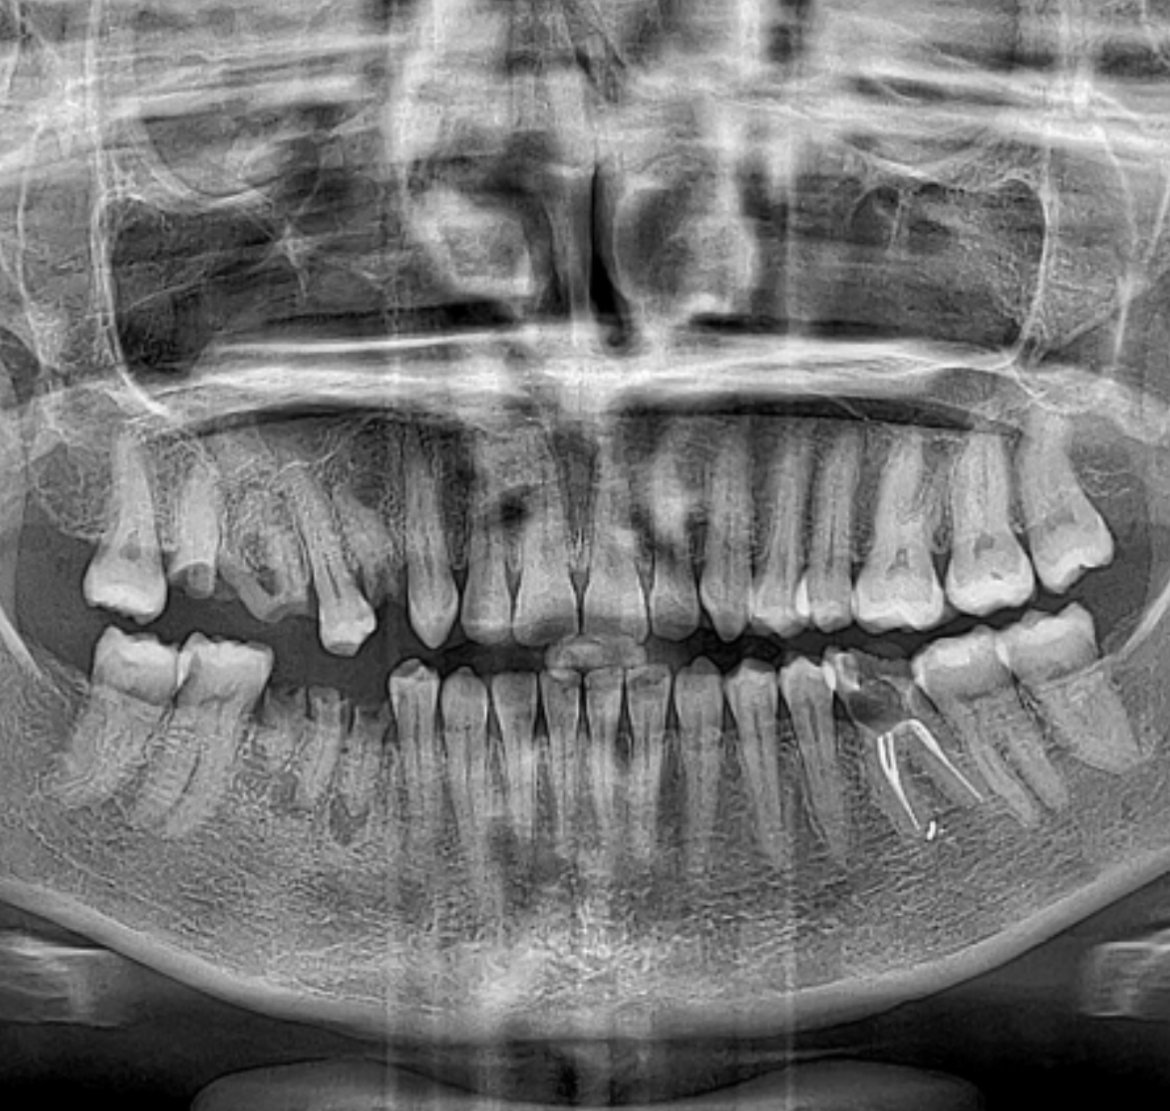

Здравейте отново! Това е панорамна снимка на момче с аутизъм. Кажете колко е зле работата, за счупените зъби знам, но другото ме притеснява.

Ами той е невербален, но посочва в горната челюст и прави болезнени физиономии 😭